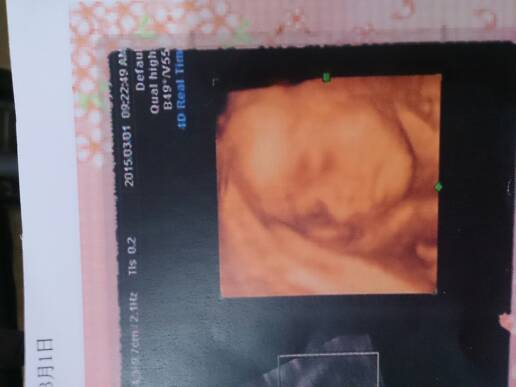

今天做的四维,宝宝一切正常开心 今天做的四维,宝宝一切正常开心 点击展开 刘明芳 2015-03-01 20:13 为您推荐: 其他回答 为宝妈开心 小乖。。 2015-03-01 22:04 恭喜恭喜。 you belong with me,, 2015-03-01 20:54 祝宝妈好孕 小甜猫 2015-03-01 20:28 你好,如果行四维彩超进行检查后,结果比较正常的话,可以判断胎儿肢体发育和内脏器官发育比较正常的,平时需要注意休息,加强营养。 cn#BBVGkaafBB 2015-03-01 20:23 新年,快乐 宝贝? 2015-03-01 20:22 加载更多 相关问题 今天做的四维,孩子一切正常 怀孕80天了,今天去医院做了b超,我都看到宝宝的胳膊了,很开心